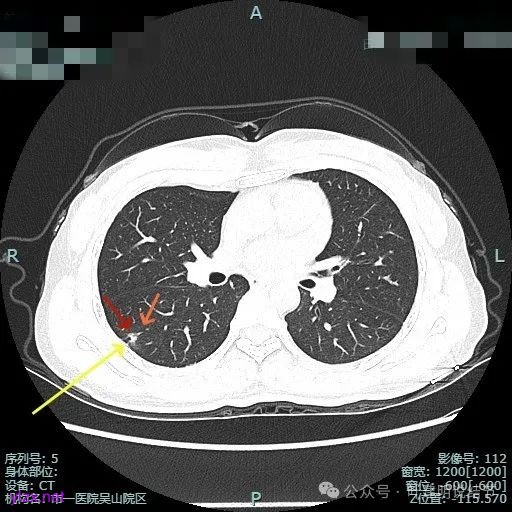

病灶部分囊壁是混合磨玻璃成分的,整体轮廓较清。

边缘区也有偏实性成分,磨玻璃成分也还是明显的,有微小血管进入。

靶重建的影像上看,病灶的囊壁明显厚薄不均,有小血管进入,一侧的边似就是斜裂的样子。

囊壁有磨玻璃成分,边缘毛糙,有少许偏实性成分,仍有磨玻璃成分。